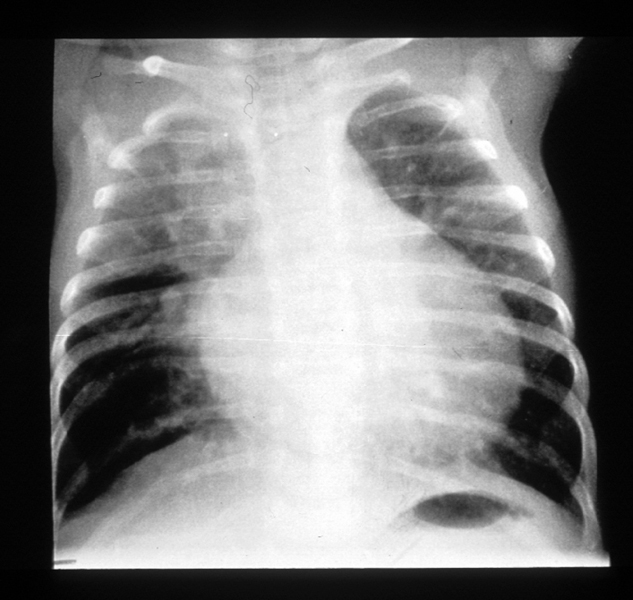

Congenital pneumonias are usually part of a transplacental infection, while neonatal pneumonias can evolve from intrauterine or postnatal acquisition. ... Retrieve Full Source

Neonatal Pneumonia - InTechOpen

Congenital or intrauterine pneumonia can be considered a variant of early onset pneumonia (2). Other classifications refer to the underlying pathogen, like bacterial or viral pneu monia or the pattern of lung infiltrates (e.g. ... Fetch Doc